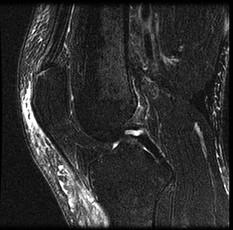

问题 男,39岁,右膝关节有外伤史,感膝关节疼痛,活动后加剧,请结合所提供的图像,选择最佳选项 ( )

选项 A、胫骨骨折 B、后十字韧带撕裂 C、前十字韧带撕裂 D、内侧半月板撕裂 E、未见异常

答案 B